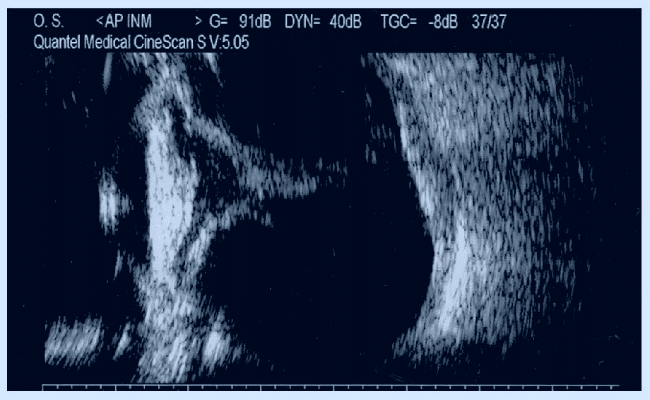

Oftalmología

En oftalmología se utiliza el ecógrafo para detectar diferentes patologías en el globo ocular